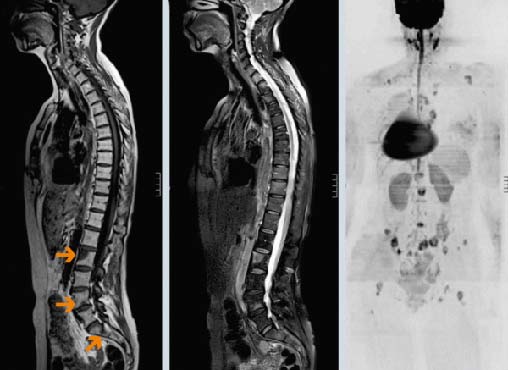

Диагностика метастазов в позвоночнике

Основные методы диагностики — КТ и МРТ. Они позволяют детально визуализировать структуры позвоночника и опухолевую ткань. Рентгенография менее информативна, так как показывает только костные структуры. Обычно ее используют при подозрении на патологический перелом.

Многие виды рака метастазируют в кости, чаще всего в позвонки. Опухолевые клетки распространяются гематогенно — с кровью. Вторичные очаги ослабляют костную ткань, что может привести к патологическим переломам позвонков, сильным болям и сдавлению спинного мозга.

В 95% случаев метастазы в позвоночнике являются экстрадуральными, то есть находятся за пределами твердой мозговой оболочки. Более половины случаев локализуются на разных уровнях позвоночного столба.

- 14.11.2014: рентгенография показала метастазы в позвоночнике.